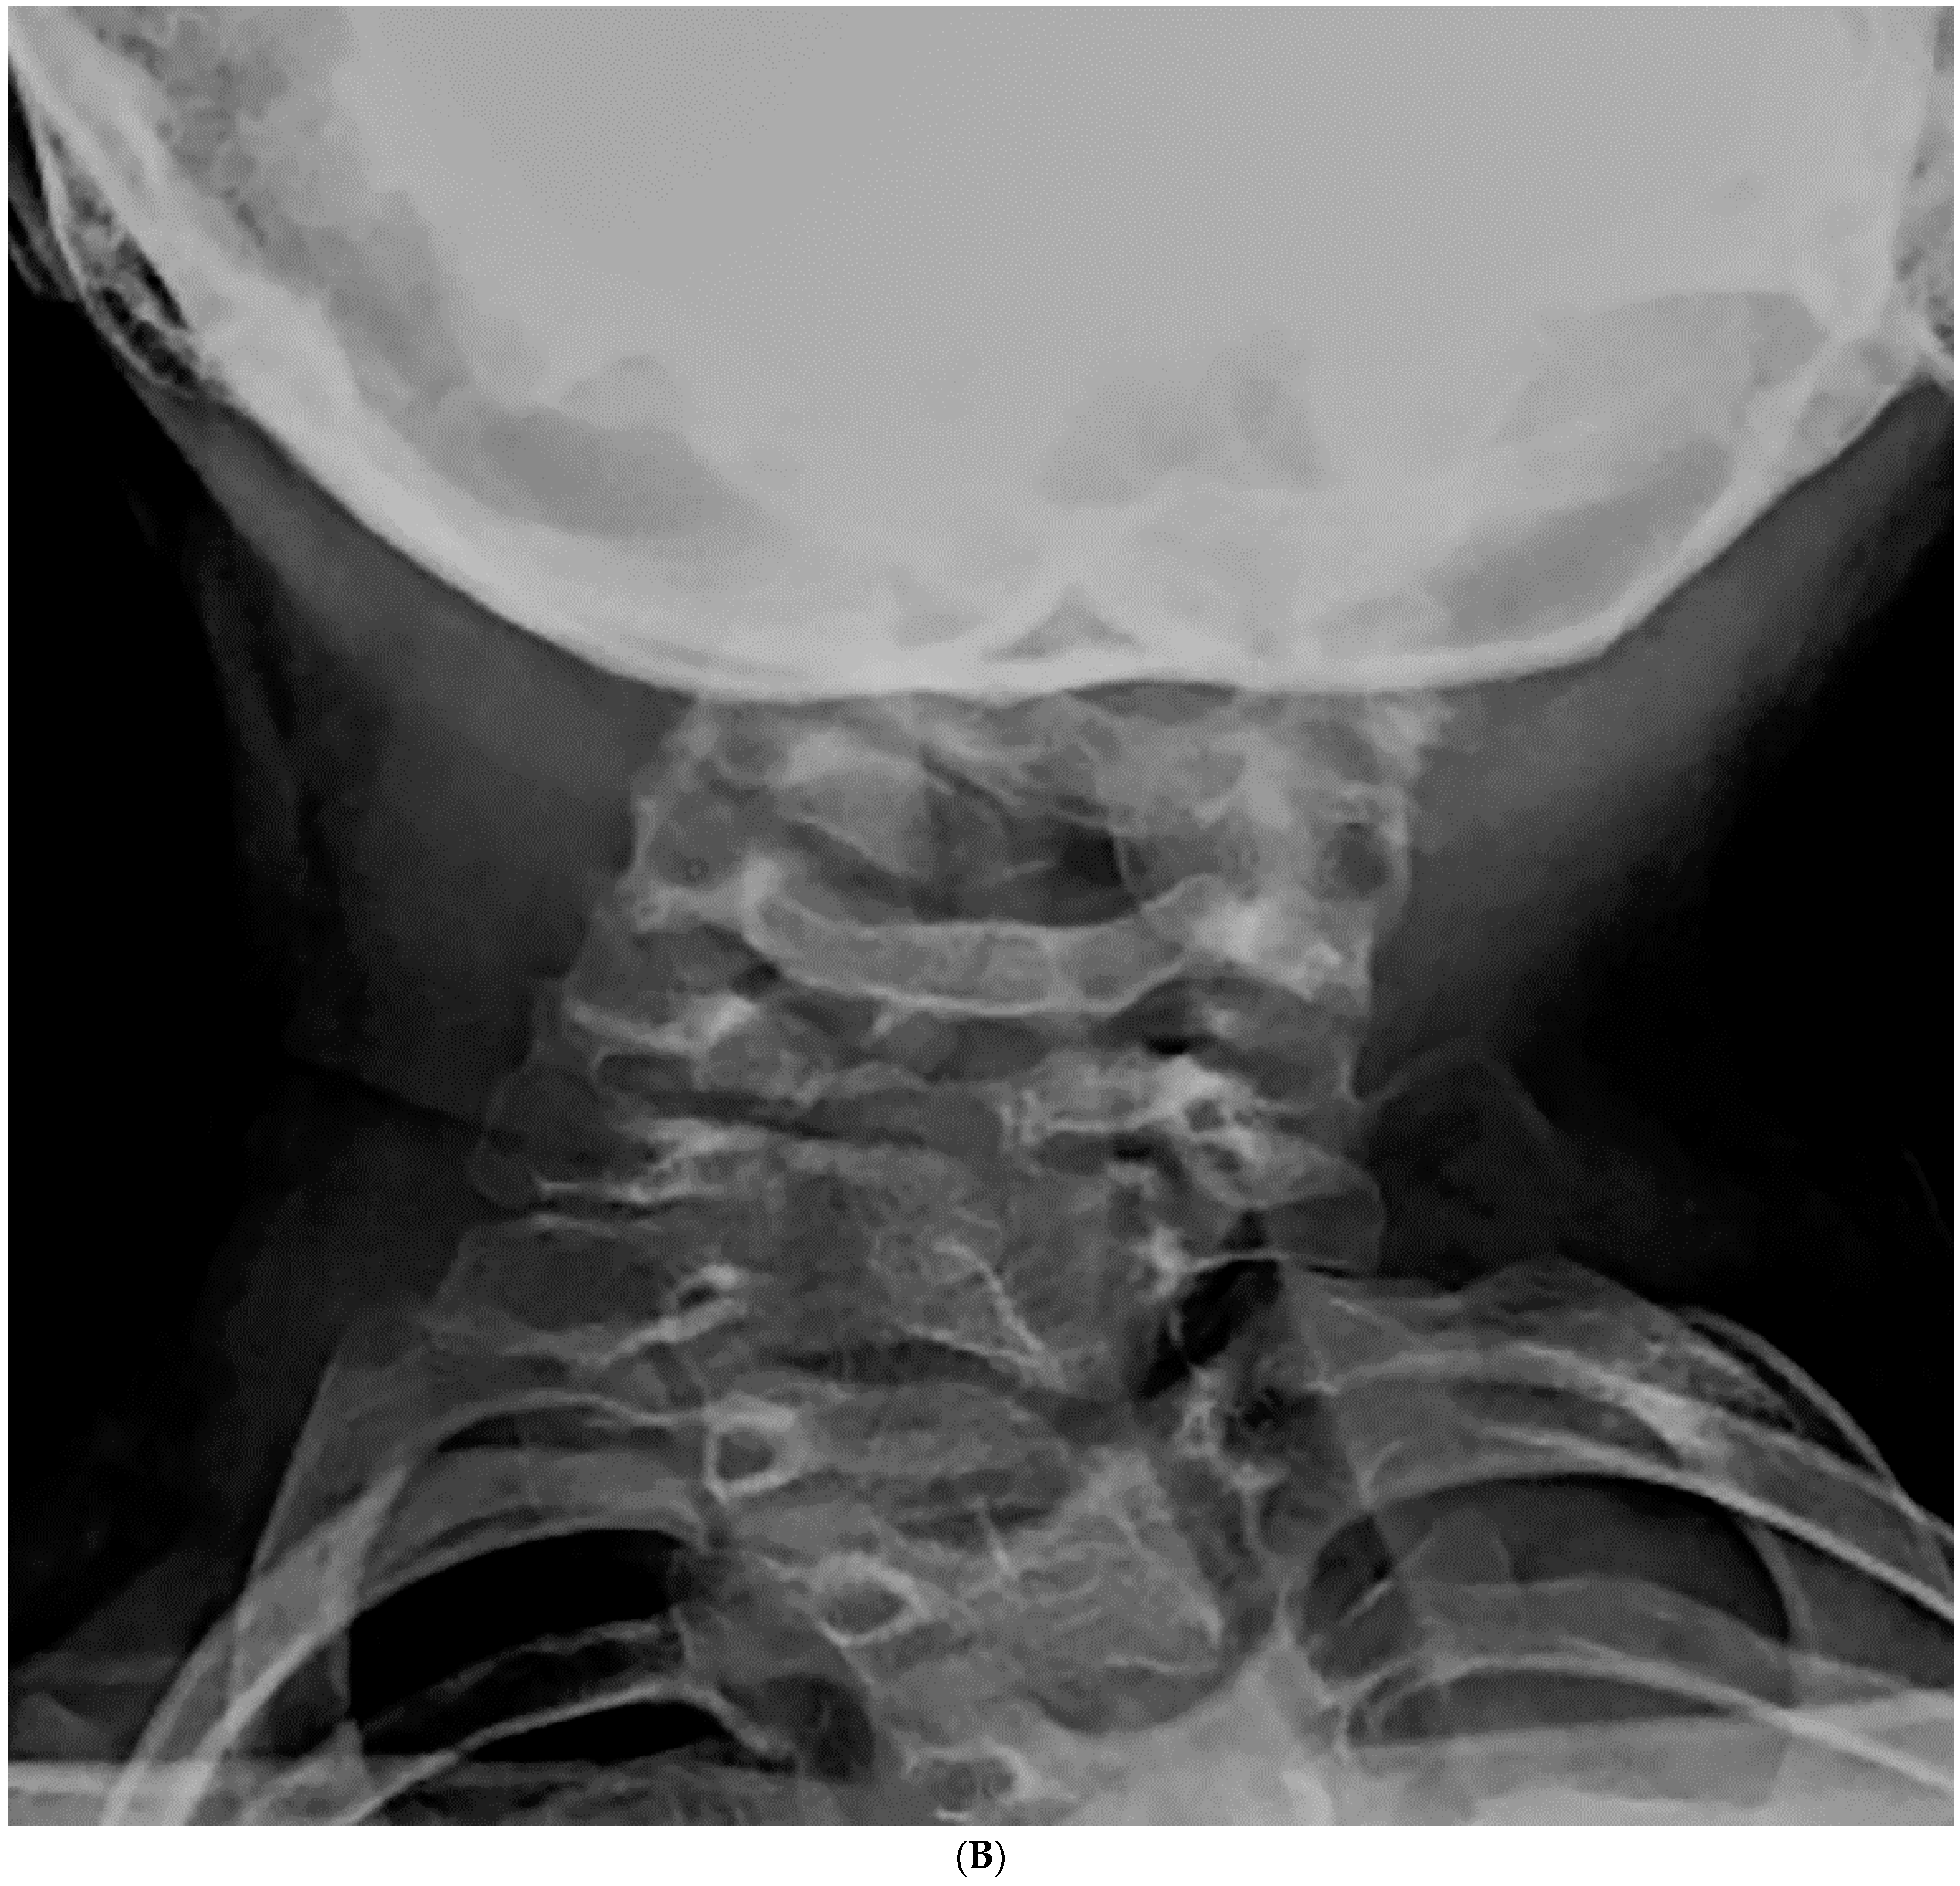

Risk Factors for Progression of Cervical Congenital Scoliosis and Associated Compensatory Curve Behavior

3. Results